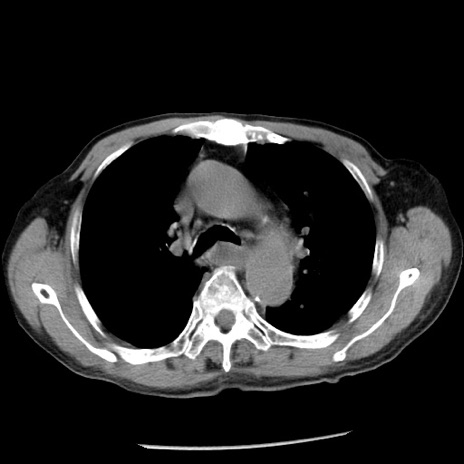

症例26(横断像)

【症例】80歳代男性

【主訴】嘔吐

【現病歴】昨晩2回嘔吐あり、今朝になっても嘔吐あり。来院。

【既往歴】胃潰瘍

【身体所見】意識清明、BT 37.6℃、BP 166/95mmHg、HR 100bpm、SpO2 97%、腹部:平坦・軟、腸蠕動音聴取良好、圧痛なし。

【データ】WBC 21900、CRP 1.46